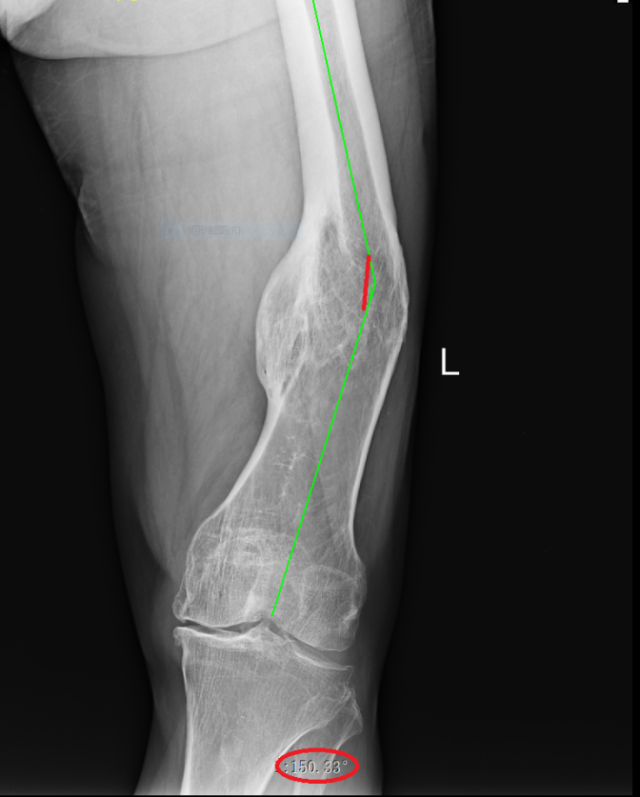

术前X线片(内翻成角30°)

武明鑫教授为其仔细体格检查,发现患者左大腿中下段外侧可见一处12cm陈旧性切口疤痕,膝关节内翻畸形,大腿中下段向外成角,膝关节内外侧局部压痛,内侧尤为明显,未触及骨擦感及反常活动,肌力Ⅳ级,肌张力降低,左下肢较右下肢缩短约5.0厘米。拍X射线片检查示:1.左股骨中下段骨质膨隆并股骨弯曲,考虑是左股骨中下段骨折畸形愈合。2.左侧膝关节退行性变。